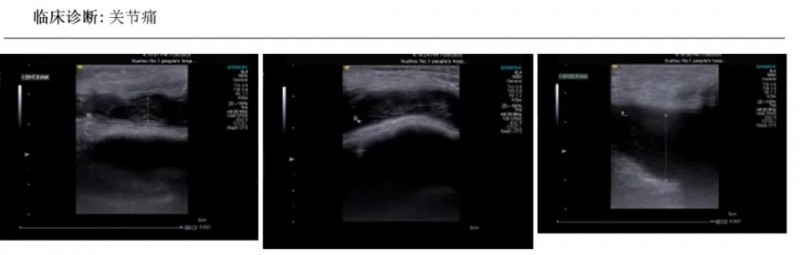

步骤一、关节超声评估:

右膝关节髌上囊及内、外侧隐窝液性暗区,较深处约22cm,内部透声差。右膝关节可见滑膜增厚,较厚处约7.3mm,CDFI:内示少许血流信号。